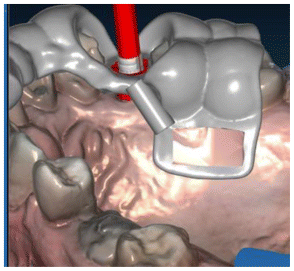

Case planning was done on Realguide 5.0 (3 diemme, Varese, Italy). The sinus lift was planned on a tooth-supported guide with an extension over the bone in the window region (Figure 1).

Two implants were planned: C-tech 3.8*9 in the sinus lift zone and 3.8*11 in element 14 (Esthetic Line-EL®, C-Tech, Bologna, Italy).